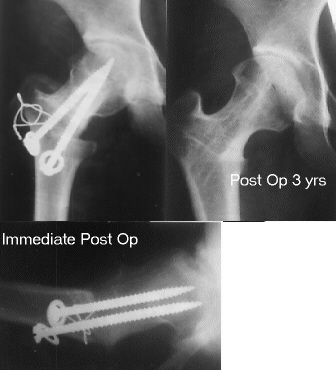

A Sugioka osteotomy was performed with 90 degrees of anterior

rotation and 15 degrees of varus angulation. After post-operative

non-weight-bearing for 4 weeks, and partial-weight-bearing for

6 weeks, she has had neither limping nor pain so far.